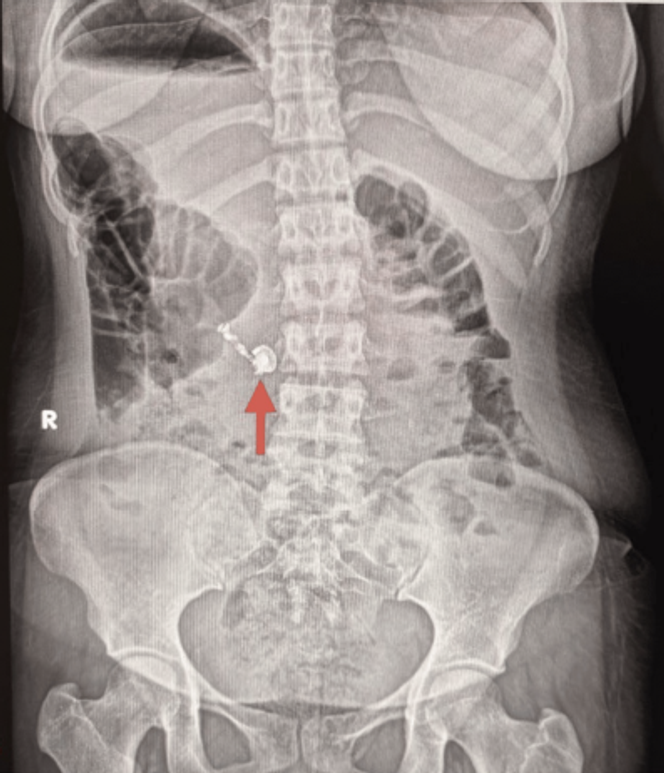

Une radiographie abdominale est réalisée. Elle localise sans ambiguïté le corps étranger. L’écouteur a déjà franchi l’estomac et se situe dans la deuxième portion du duodénum, c’est‑à‑dire au‑delà du pylore, zone de transition entre l’estomac et l’intestin grêle. Or le profil de risque change de façon notable dès qu’une pile, ou un dispositif qui en contient une, a dépassé l’estomac. Plusieurs études montrent que, chez des patients asymptomatiques, les piles situées au‑delà du pylore peuvent souvent être prises en charge de façon conservatrice, sous simple surveillance rapprochée.

Après discussion multidisciplinaire, les médecins optent pour une prise en charge conservatrice, fondée sur une surveillance clinique rapprochée et des radiographies répétées, plutôt que sur une endoscopie en urgence. Plusieurs éléments plaident en faveur de cette stratégie de surveillance (« wait-and-watch ») : le fait que l’objet a déjà dépassé le pylore, ce qui réduit le risque d’exposition prolongée de l’estomac et de lésions liées à la batterie, ainsi que le caractère non tranchant du corps étranger à l’imagerie et l’absence persistante de symptômes chez la patiente.